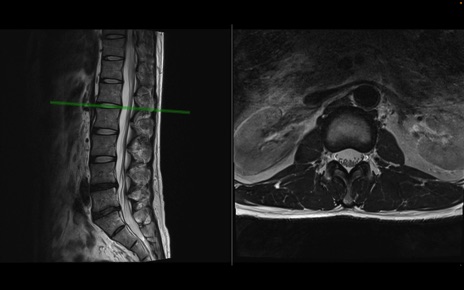

【整形】TIPS症例1 腰椎MRI 横断像と矢状断像

【症例】40歳代男性

【主訴】左臀部〜大腿後面痛み

【現病歴】2週間前から腰痛あり。2日前に夜中にくしゃみをした際に激痛が出現。疼痛強いため来院。

【身体所見】左臀部〜大腿後面、下腿後面のしびれ。SLR -/+ 30度、うつ伏せ困難、筋力低下なし。

異常所見と診断は?